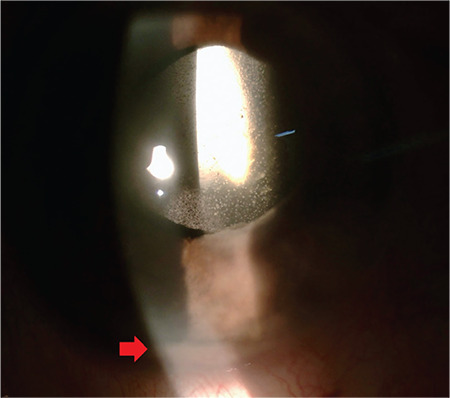

A 78-year-old man with a history of lung cancer, chemotherapy, radiotherapy, and coronavirus disease 2019 infection experienced visual deterioration of two-weeks’ duration in his right eye. There was multifocal, yellowish-white retinitis foci, vascular engorgement, and scattered intraretinal hemorrhages extending from posterior pole to retinal periphery in the right eye, whereas the left eye was normal. Intravitreal vancomycin, ceftazidime, clindamycin, and dexamethasone were given for endogenous endophthalmitis initially. Vitreous culture confirmed the presence of Aspergillus lentulus, and he was treated with intravitreal amphotericin-B and voriconazole injections together with systemic amphotericin-B, voriconazole, posaconazole, and micafungin therapy. During follow-up, vitreoretinal surgery was performed because of rhegmatogenous retinal detachment, and he received one additional cycle of chemotherapy due to recurrence of the cancer. Although the retina was attached, enucleation was eventually required due to painful red eye. Atypical squamous cells beneath the neurosensory retina suggesting metastasis were noted on histopathological examination. Timely ocular examination is crucial for any immunocompromised patient having ocular symptoms. High level of suspicion for a fungal etiology is a must in these patients.